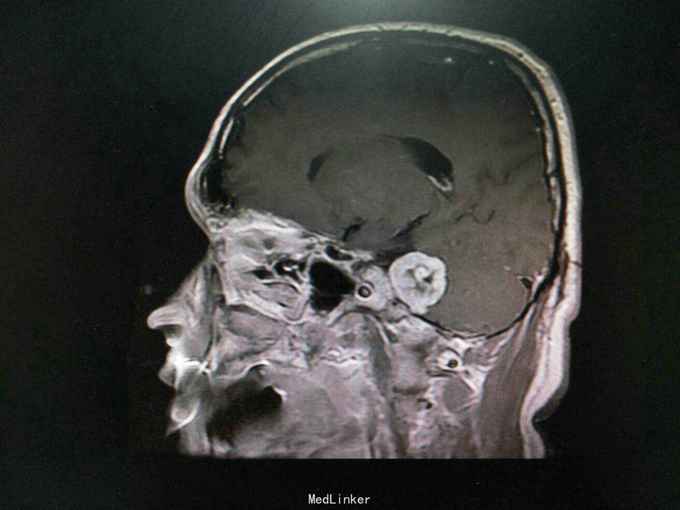

查体:生命体征平稳。神经系统检查提示:Ⅴ颅神经:右侧面部感觉稍减退,张口下颌无偏歪 。Ⅷ颅神经:右侧听力较左侧减退,无眩晕 。外院检查示行磁共振检查提示:右侧桥脑小脑角占位:听神经鞘瘤?辅助检查:颅脑MRI检查提示:右侧桥小脑角处可见类圆形占位性病变,边界清,形态规则,大小约24.8mm×33.8mm。右侧桥小脑角区占位,考虑听神经鞘瘤。

诊断:听神经鞘瘤 处理:右侧枕下乙状窦后入路听神经瘤切除术